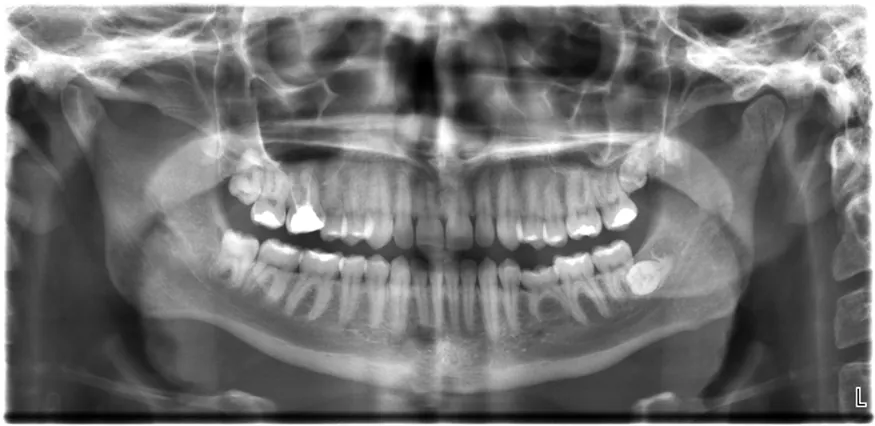

All of us can identify diagnostic uses of x-ray photons. Among these are the universal dental and medical x rays that have become an essential part of medical diagnostics. (See Figure 30.25 and Figure 30.26.) X rays are also used to inspect our luggage at airports, as shown in Figure 30.24, and for early detection of cracks in crucial aircraft components. An x ray is not only a noun meaning high-energy photon, it also is an image produced by x rays, and it has been made into a familiar verb—to be x-rayed.

The X-ray image of front view of the jaw, especially the teeth.

Figure 30.24 An x-ray image reveals fillings in a person’s teeth. (credit: Dmitry G, Wikimedia Commons)